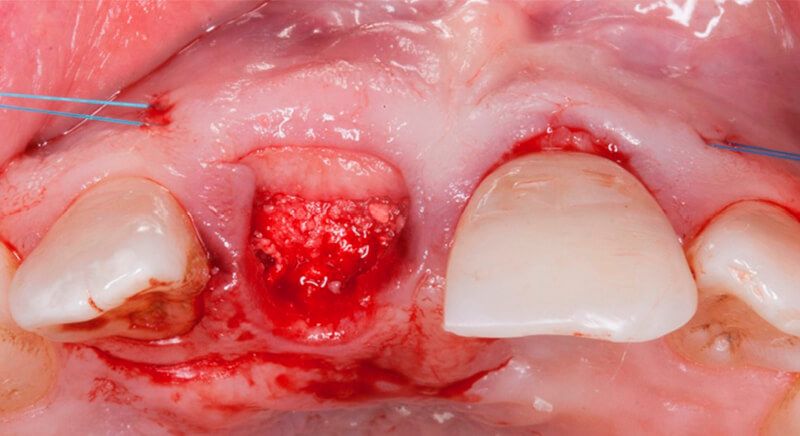

The guided surgery was performed by lifting a full thickness mucoperiosteal flap. A Biomimetic Ocean CC implant, diameter 3.5mm and length 10mm, was inserted using the surgical guide in the ideal three-dimensional position and the defects were regenerated with xenograft and reabsorbable membrane, the nasopalatine duct on the palatine side and the area of dehiscence on the vestibular.

During the same surgical intervention, a short 3mm Avinent healing abutment was positioned and fully covered by the flap. Primary closure was completed and we waited 6 months for the bone graft to mature.